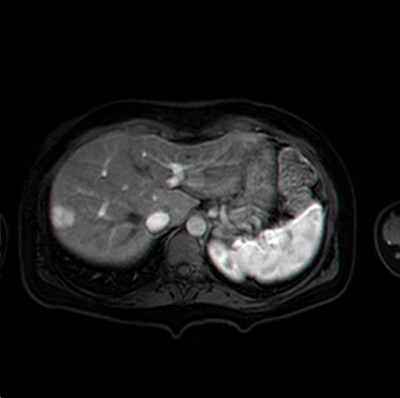

בבדיקות מעבדה: תפקודי הכבד לרוב תקינים, אך תיתכן עליה קלה ברמת האנזימים. האבחנה מתבצעת על ידי טומוגרפיה ממוחשבת (תמונה 26.10 ) או תהודה מגנטית (תמונה 27.10) כך שבדרך כלל אין צורך לקחת ביופסיה. באולטרה-סאונד ניתן להדגים גוש בכבד (תמונה 28.10).

|

| תמונה 28.10 : הדגמה של FNH באולטרה-סאונד כבד. השנתות מצביעות על גודל השאת. |

|---|